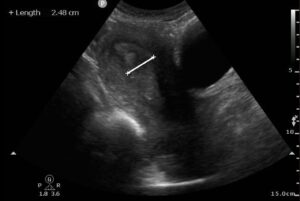

A 58-year-old male presents with 1 day of severe vertigo associated with nausea and vomiting, tinnitus, and sudden-onset hearing loss. He reports several days of left-sided ear pain and discharge from his left ear. Vital signs reveal T 38.9C, HR 120, BP 138/96, RR 18, SpO2 99% on room air. He...